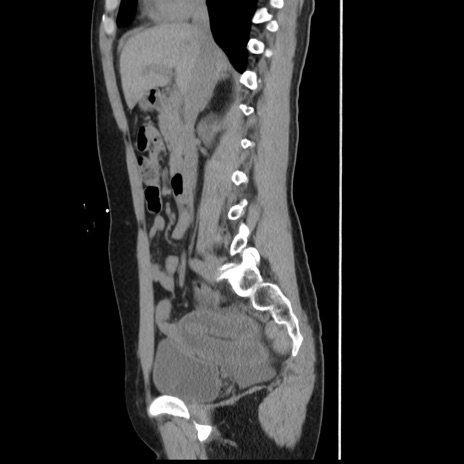

症例10(矢状断像)

【症例】 50歳代女性

【主訴】 腹痛

【現病歴】前日生レバーを食べた。今朝に排便あり。 昼前に突然発症の腹痛を生じ、当院救急外来を受診した。

【既往歴】 子宮筋腫にてで子宮全摘後

【身体所見】 意識清明、腹部:平坦、軟、下腹部やや左を中心に圧痛・反跳痛あり、筋性防御あり

【データ】WBC 7800、CRP 0.07